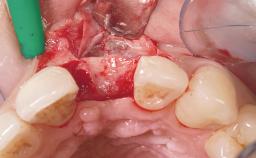

Immediate Flapless Placement of an Implant in a Maxillary Left Central Incisor Site

A 42-year-old female patient was referred to our clinic at the School of Dentistry of the University of São Paulo in November 2004, presenting a deficient restoration in the upper left central incisor. The clinical examination revealed no gingival retraction or any signs of gingival inflammation and, therefore, previous periodontal treatment was not considered. The patient presented a high lip line at full smile and a thin tissue biotype. This combination characterized a high-risk situation from an anatomic point of view, which required careful preoperative planning and cautious surgical execution.

Soft Tissue Grafting None

Soft Tissue Contour and Volume Ideal